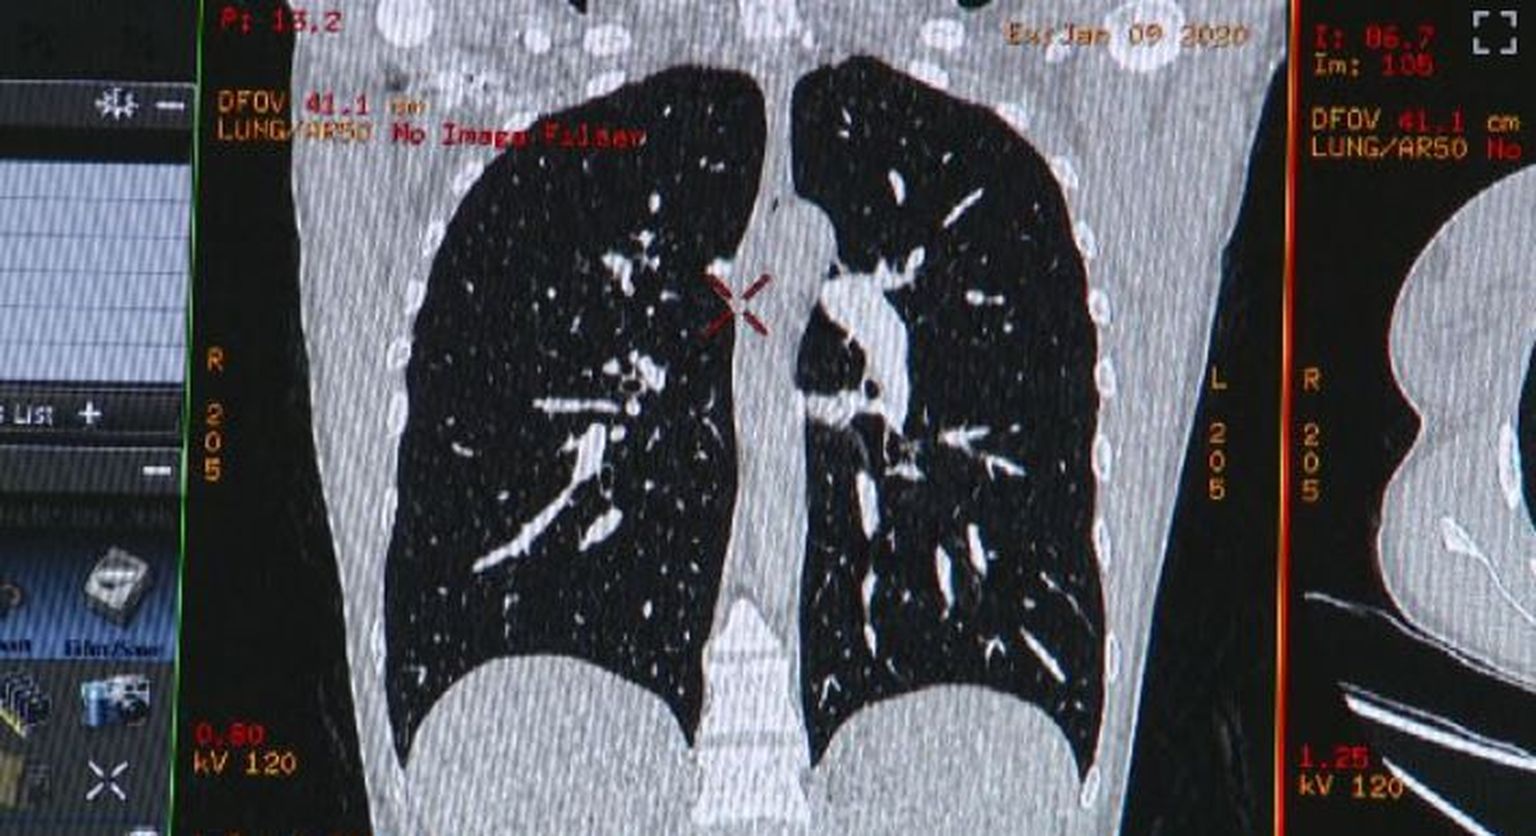

• Snimke raka - 2 Foto: DNEVNIK.hr

• Snimke raka - 1 Foto: DNEVNIK.hr